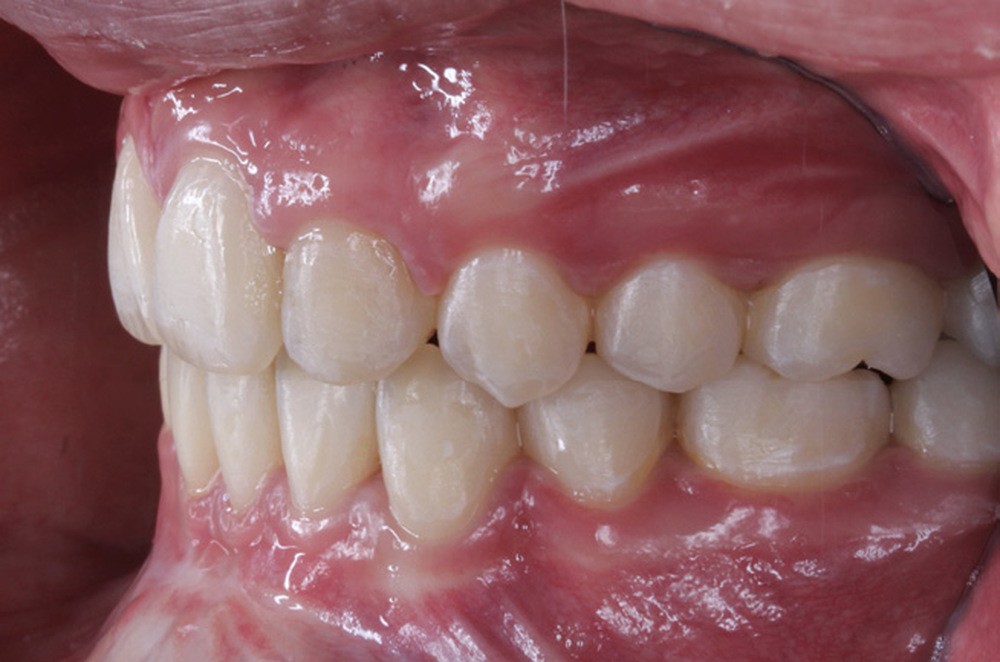

La patiente âgée de 14 ans et 6 mois le jour du bilan se présente en consultation pour une gêne esthétique au niveau de ses dents maxillaires : « trop en avant et avec des espaces ».

Les examens cliniques et radiologiques ont mis en évidence l’inclusion de 13 et 23, une légère classe II bilatérale par perte d’ancrage, un biotype parodontal de type IV de Maynard et Wilson avec une insertion du frein mandibulaire antérieur papillaire, une biproalvéolie et une typologie hypodivergente. La réalisation d’un examen tridimensionnel a permis de confirmer la localisation palatine de 23 et vestibulaire de 13 ainsi que de visualiser l’étendue des résorptions radiculaires touchant 12, 21 et 22 (fig. 1a-i).